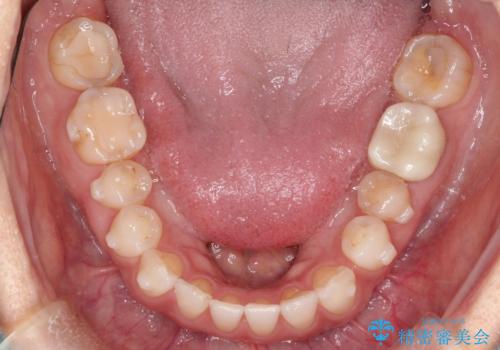

- 過去に矯正を行ったあと、前歯の後戻りを主訴に来院されました。

マウスピース矯正にて隙間を閉じる計画をたて、治療を行いました。